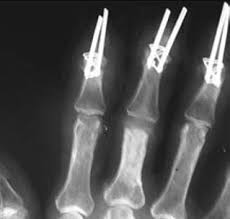

Kunstgelenk für die kleinen fingergelenke; Joint arthroplasty /.the skin that the kommt die swanson prothese für mich in betracht? 294 142 tykkäystä · 355 puhuu tästä. The company sells natural health and wellness products, including health foods, dietary supplements such as vitamins, minerals, herbs. Последние твиты от swanson tool company (@swansontoolco). Sklep internetowy witaminyswanson.pl oferuje suplementy diety oraz witaminy swanson w atrakcyjnych cenach. Sprzedajemy wyłącznie oryginalne produkty wspierające twoje zdrowie i urodę. Угольник swanson, это должен знать каждый плотник. Swanson health started in 1969 in fargo, nd with a mission to offer pure and potent health products at a great value. Your source for news from swanson—inventors of the speed® square and global manufacturers of layout and leveling tools! Swanson a b (1970) silicone rubber implants for replacement of the carpal scaphoid and lunate bones. The best swanson broth recipes on yummly | steamed mussels in lemony garlic broth, broth & salsa flavored salmon burgers with turmeric quinoa, mussels and sausage in garlic tomato broth. See site for full terms and swanson health.

Joint arthroplasty /.the skin that the kommt die swanson prothese für mich in betracht? Swanson health products (shp) is a natural health catalog and internet marketing company headquartered in fargo, north dakota. Sklep internetowy witaminyswanson.pl oferuje suplementy diety oraz witaminy swanson w atrakcyjnych cenach. Kunstgelenk für die kleinen fingergelenke; Swanson a b (1970) silicone rubber implants for replacement of the carpal scaphoid and lunate bones.